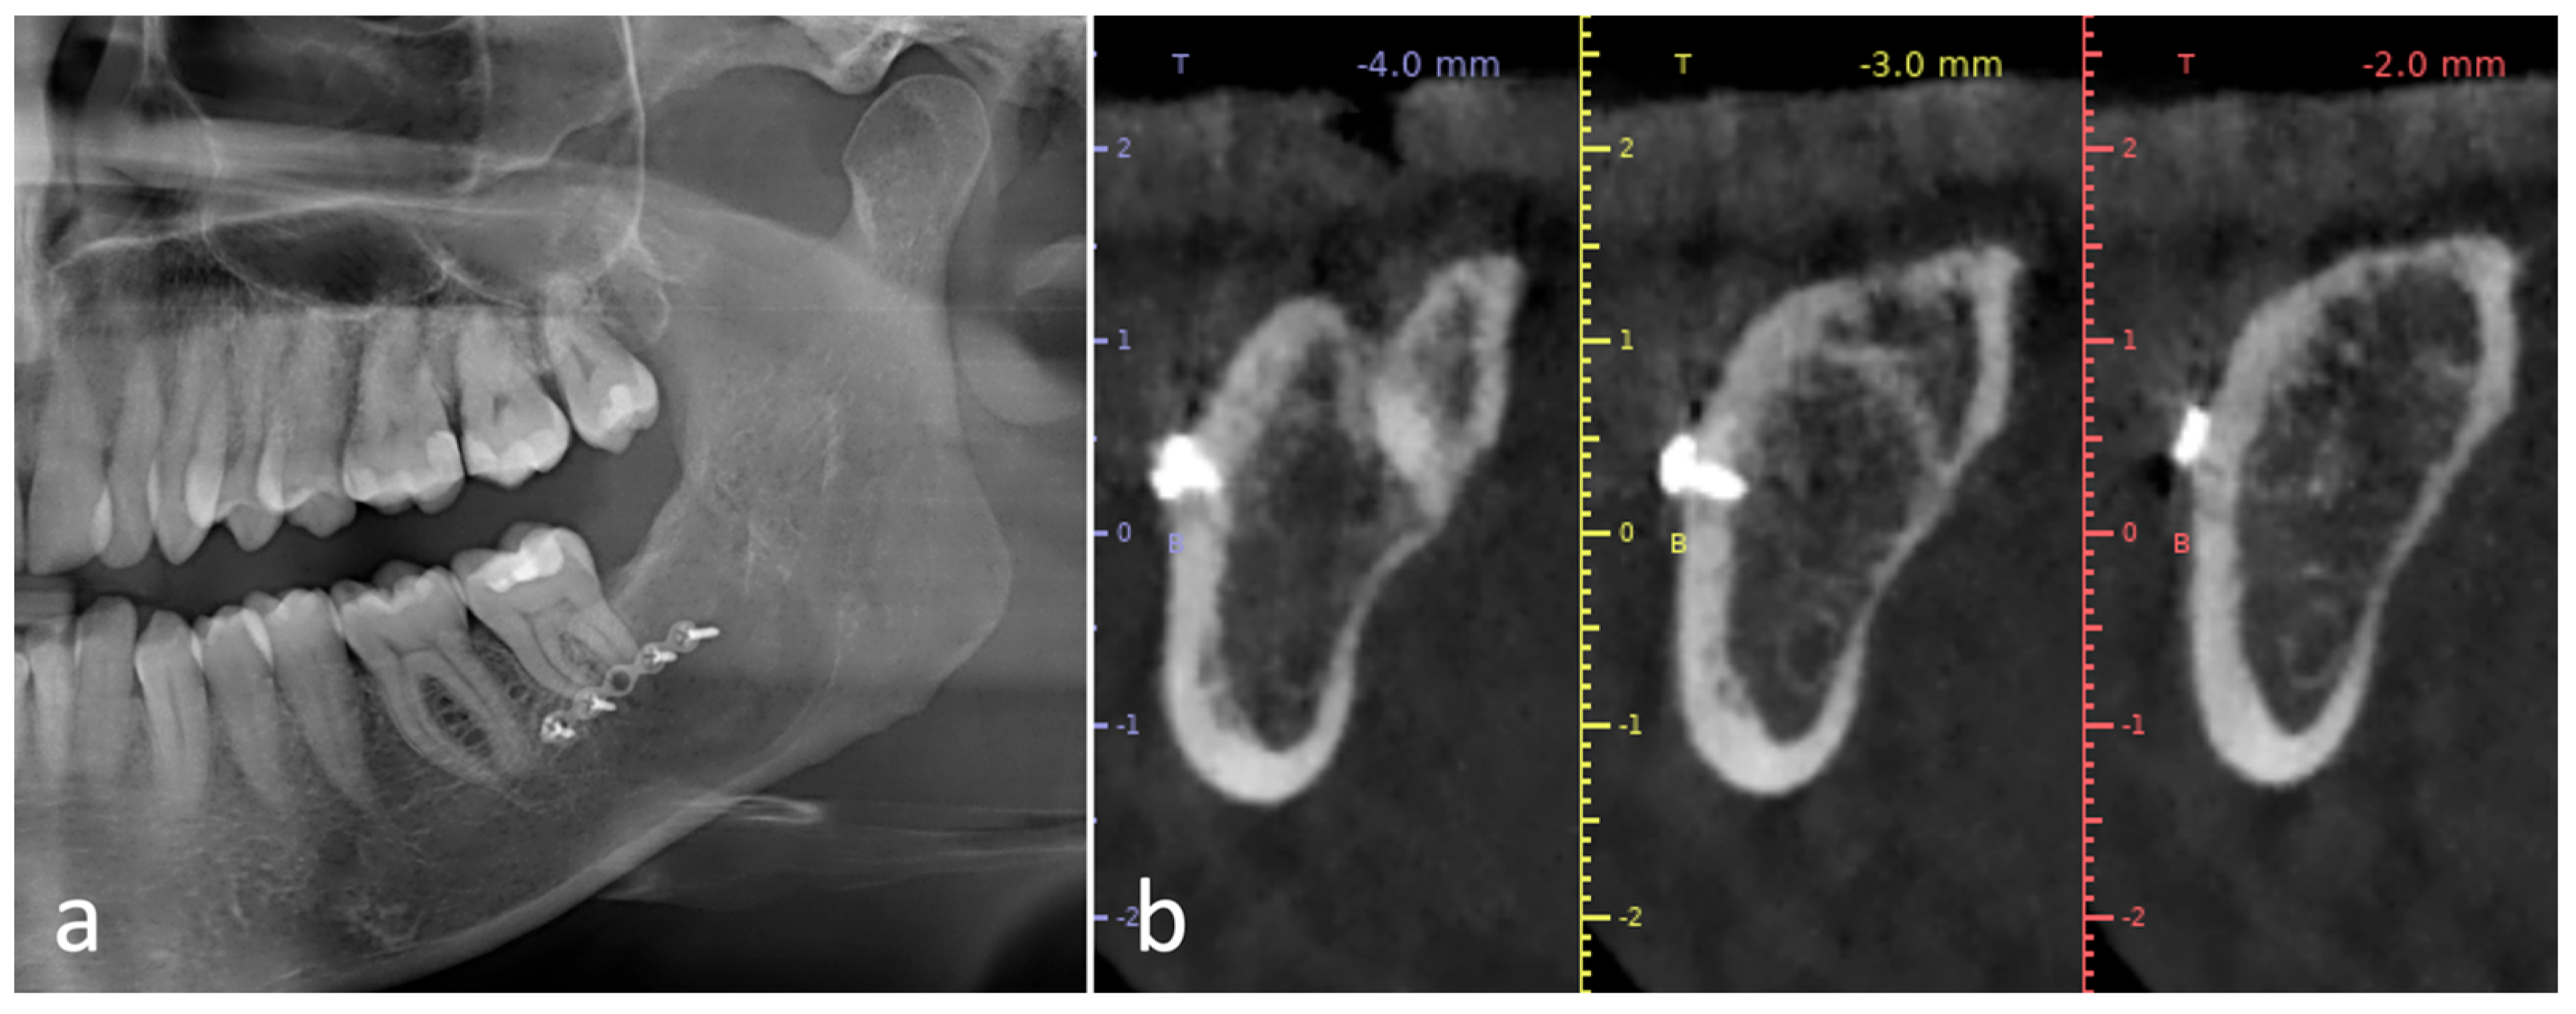

Figure 2.

Case 2. Impacted tooth 38 with periodontal probing distal to 37. (a) Preoperative orthopantomography; (b,c) details of the CT scan demonstrating the consistent thickness of the buccal wall and the proximity to the mandibular canal; (d) surgical guide planning; (e,f) surgical guide with the fixation screw inserted.

Two patients were referred for the extraction of clinically asymptomatic impacted left mandibular third molars. Informed consent was obtained and the two cases belonging to the case collection were approved by the Padova Hospital Ethical Review Board (Prot. 3719/AO/2016). The first patient, a 47-year-old healthy male, was referred for the suspicion of an odontogenic cyst associated with a horizontally oriented impacted tooth 38 incidentally discovered on a panoramic radiograph (case 1) (Figure 1). Case 2 consisted of a horizontally oriented deeply impacted tooth 38 in a 31-year-old healthy male patient, responsible for an increased probing depth distal to the adjacent second molar. In both cases, the unerupted teeth were close to the mandibular canal (Figure 2). Preoperative cone-beam computed tomography (CBCT) was performed in both cases, and the main inclusion criteria for the adoption of the technique were evaluated, namely, the considerable thickness of the buccal bone cortex at multiple points, i.e., >2 mm, and the need to enhance the control of the operatory field in the presence of anatomical limits (inferior alveolar nerve). CBCT allowed the design and production of a 3D printed surgical guide following the SafeCut® workflow (SafeCut®, GuidedSurgery2.0 s.r.l., Padova, Italy).